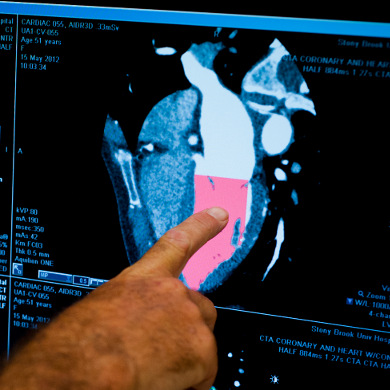

Coronary Artery Disease

Coronary artery disease (CAD) occurs when the arteries that bring blood to the heart muscle (coronary arteries) become hardened and narrowed. CAD is the most common type of heart disease and may also be known as coronary heart disease (CHD), heart disease and ischemic heart disease.